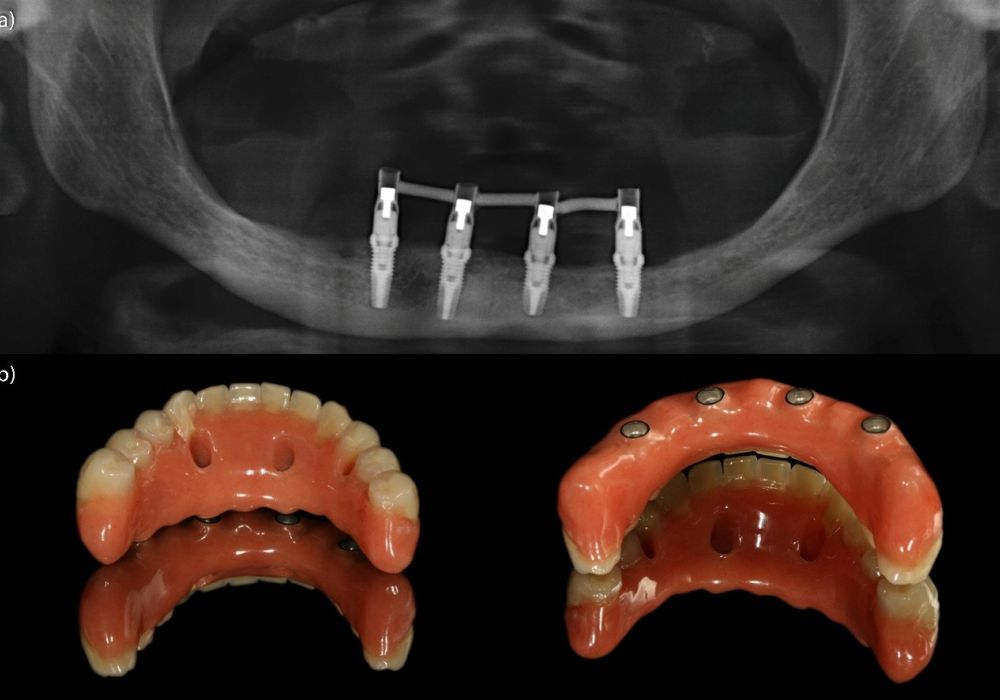

Colocación de implante postextracción con provisionalización inmediata en el sector estético: caso clínico con seguimiento a 4 años